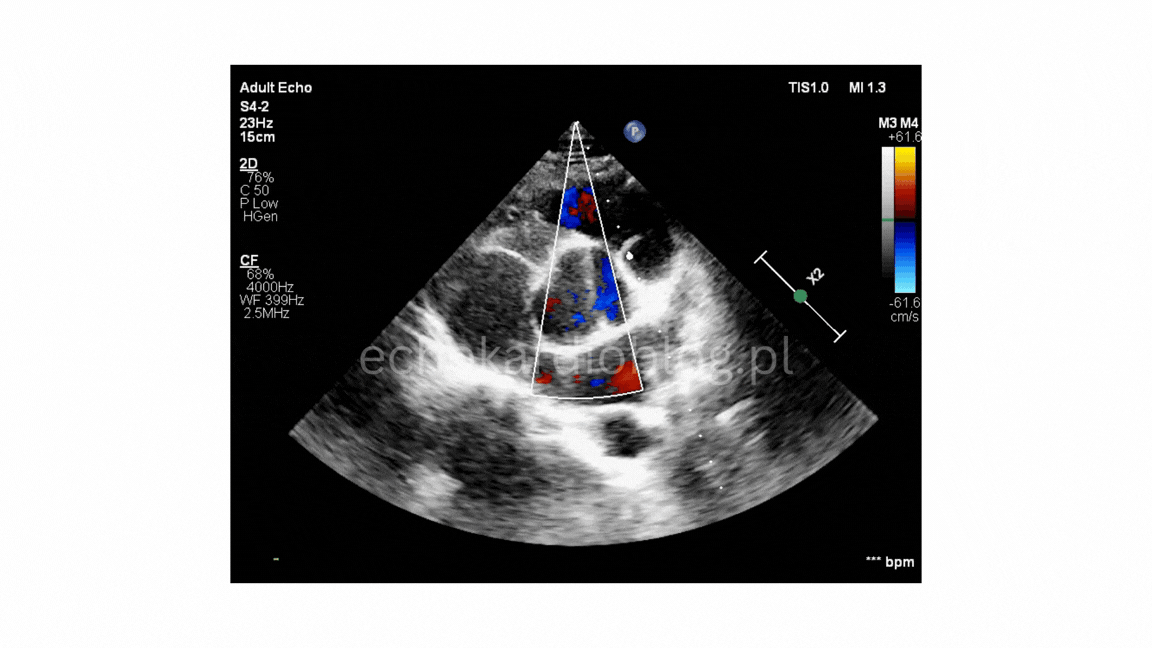

W pierwszym filmie obraz jest doskonały i budowa zastawki jest oczywista. W drugim – rozpoznanie wymaga większej uwagi i doświadczenia.

In the following three examples, I show how strongly the quality of the echocardioigraphic examination affects the ability to recognize a bicuspid aortic valve (BAV).

In the first video, the image quality is excellent, and the bicuspid morphology is obvious. In the second one, the diagnosis requires more attention and experience.